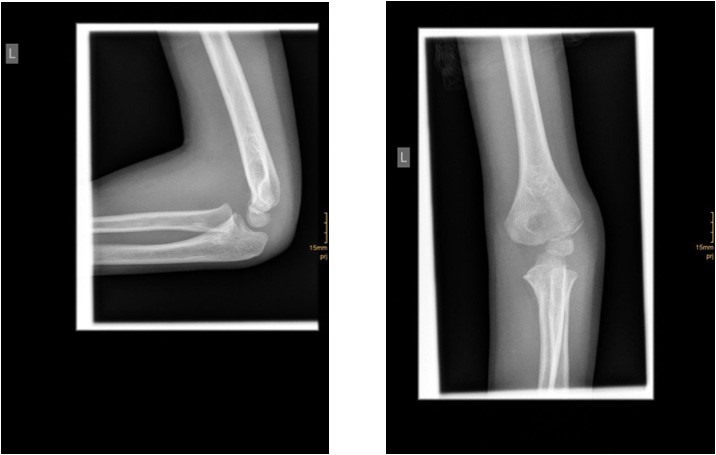

The degree of displacement may be seen on the true lateral view. In determining whether the articular hinge is intact (i.e., stage I vs. stage II), the relationship of the proximal ulna to the distal humerus is evaluated for the presence of lateral translocation. Oblique views are especially helpful in patients in whom a stage I displacement is suspected but not evident on AP and lateral views. Figure 1 and Figure 2.

Figure 1.6 year old male patient with a undislocated left lateral condyle fracture which was succesfully treated with a cast (personal collection)